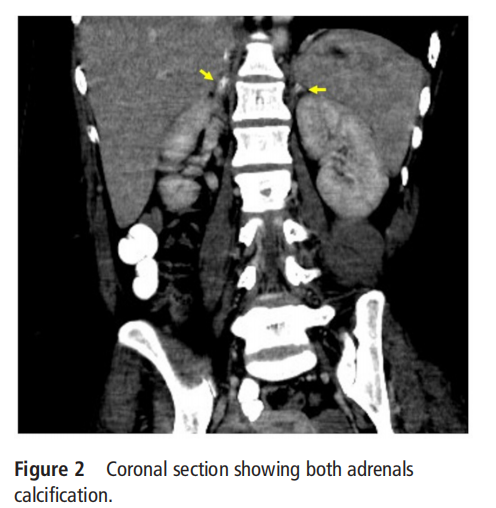

٢٠ کی دہائی میں ایک خاتون نے ہمارے سامنے گدگدی اور ہائپوٹینشن کی بار بار قسطیں پیش کیں جن کے لئے پچھلے سال میں متعدد اسپتالوں میں داخل ہونے کی ضرورت تھی۔ اس کے پیٹ میں شدید درد کی ایک قسط تھی جس کے بعد آسان فیٹیجیبلٹی، اینوریکسیا اور ترقی پسند ہائپر پیگمنٹیشن کی تاریخ تھی جو گزشتہ 1 سال کے دوران 5 کلوگرام وزن میں کمی سے وابستہ تھی۔ طبی معائنے پر، وہاں ڈفیوز ہائپر پیگمنٹیشن تھی اور اس کا بلڈ پریشر 90/50 ملی میٹر ایچ جی تھا جس میں ایک اہم پوسٹورل ڈراپ تھا۔ باقی نظامی امتحان معمول کی بات تھی۔ خون کی تحقیقات میں کم سوڈیم (125 ایم ایم او ایل/ایل)، ہائپرکلایمیا (5.5 ایم ایم او ایل/ایل)، ہائپوکورٹیسولیا (2یو جی/ڈی ایل کا 8:00 بجے کورٹیسول) اور 1250پی جی/ایم ایل > کا ایک بلند پلازما ایڈرینوکورٹیکوٹراپک ہارمون (اے سی ٹی ایچ) سامنے آیا۔ بلند اے سی ٹی ایچ کی موجودگی میں کم سیرم کورٹیسول کی موجودگی ایک پرائمری کا اشارہ تھیایڈرینل کی کمی. اس کے بعد، ایڈرینل غدود کو تصور کرنے کے لئے پیٹ کا سی ٹی اسکین کیا گیا، اور اس سے دو طرفہ چنکی کیلسیفیکیشن ظاہر ہوا جس میں شامل تھےکظریغدوددونوں اطراف سے پہلے ایڈرینل ہیمرج (اعداد و شمار 1 اور 2) کے وقوع کی تجویز دی گئی ہے۔ مزید برآں، ایک ایٹیولوجیکل ورک اپ کیا گیا تھا، جس میں ایک عام پروتھرومبن وقت اور فعال تھرمبوپلاسٹن وقت (59 کی دہائی) کے دورانیے میں طول دکھایا گیا تھا، جو عام پلازما کے اضافے کے ساتھ درست نہیں تھا۔ اسے لوپس اینٹی کوگلنٹ اور اینٹی کارڈیولیپن اینٹی باڈیز اور اینٹی باڈیز ٹو بیٹا 2 گلیکوپروٹین 1 کی موجودگی کی بنیاد پر اینٹی فاسفولیپڈ (اے پی ایل) سنڈروم کی تشخیص ہوئی تھی۔ کیے گئے دیگر خون کے ٹیسٹوں میں ایک مکمل ہیموگرام شامل تھا، جس میں ہیموگلوبن کو 10 گرام/ڈی ایل (این:13-15 گرام/ڈی ایل)، 7100/ایم ایم 3 (این:4000-11000/ایم ایم³ کی کل لیوکوسائٹ گنتی، دکھایا گیا تھا، میئن کارپسکلر ہیموگلوبن 25.2 پی جی، ریٹیکولوسائٹ کی گنتی 3.09 فیصد، تفریقی گنتی میں 77 فیصد نیوٹروفل، 1 فیصد ایوسینوفل، 13 فیصد لمفوسائٹس اور 9 فیصد مونوسائٹس ظاہر ہوئے۔ پلیٹ لیٹ کی تعداد 1.52 لاکھ/ملی میٹر ² تھی۔ ڈی ڈمر 233این جی/ایم ایل تھا۔ اس مریض میں فبرینوجن اور پلیٹ لیٹ جمع کرنے کے ٹیسٹ دستیاب نہیں تھے۔ اسے ہائیڈروکورٹیسن اور فلوڈروکورٹیسن پر شروع کیا گیا تھا۔ اے پی ایس کے لیے اس کا آغاز اینوکساپرین پر کیا گیا اور پھر وارفرین کے ساتھ چھا گیا۔